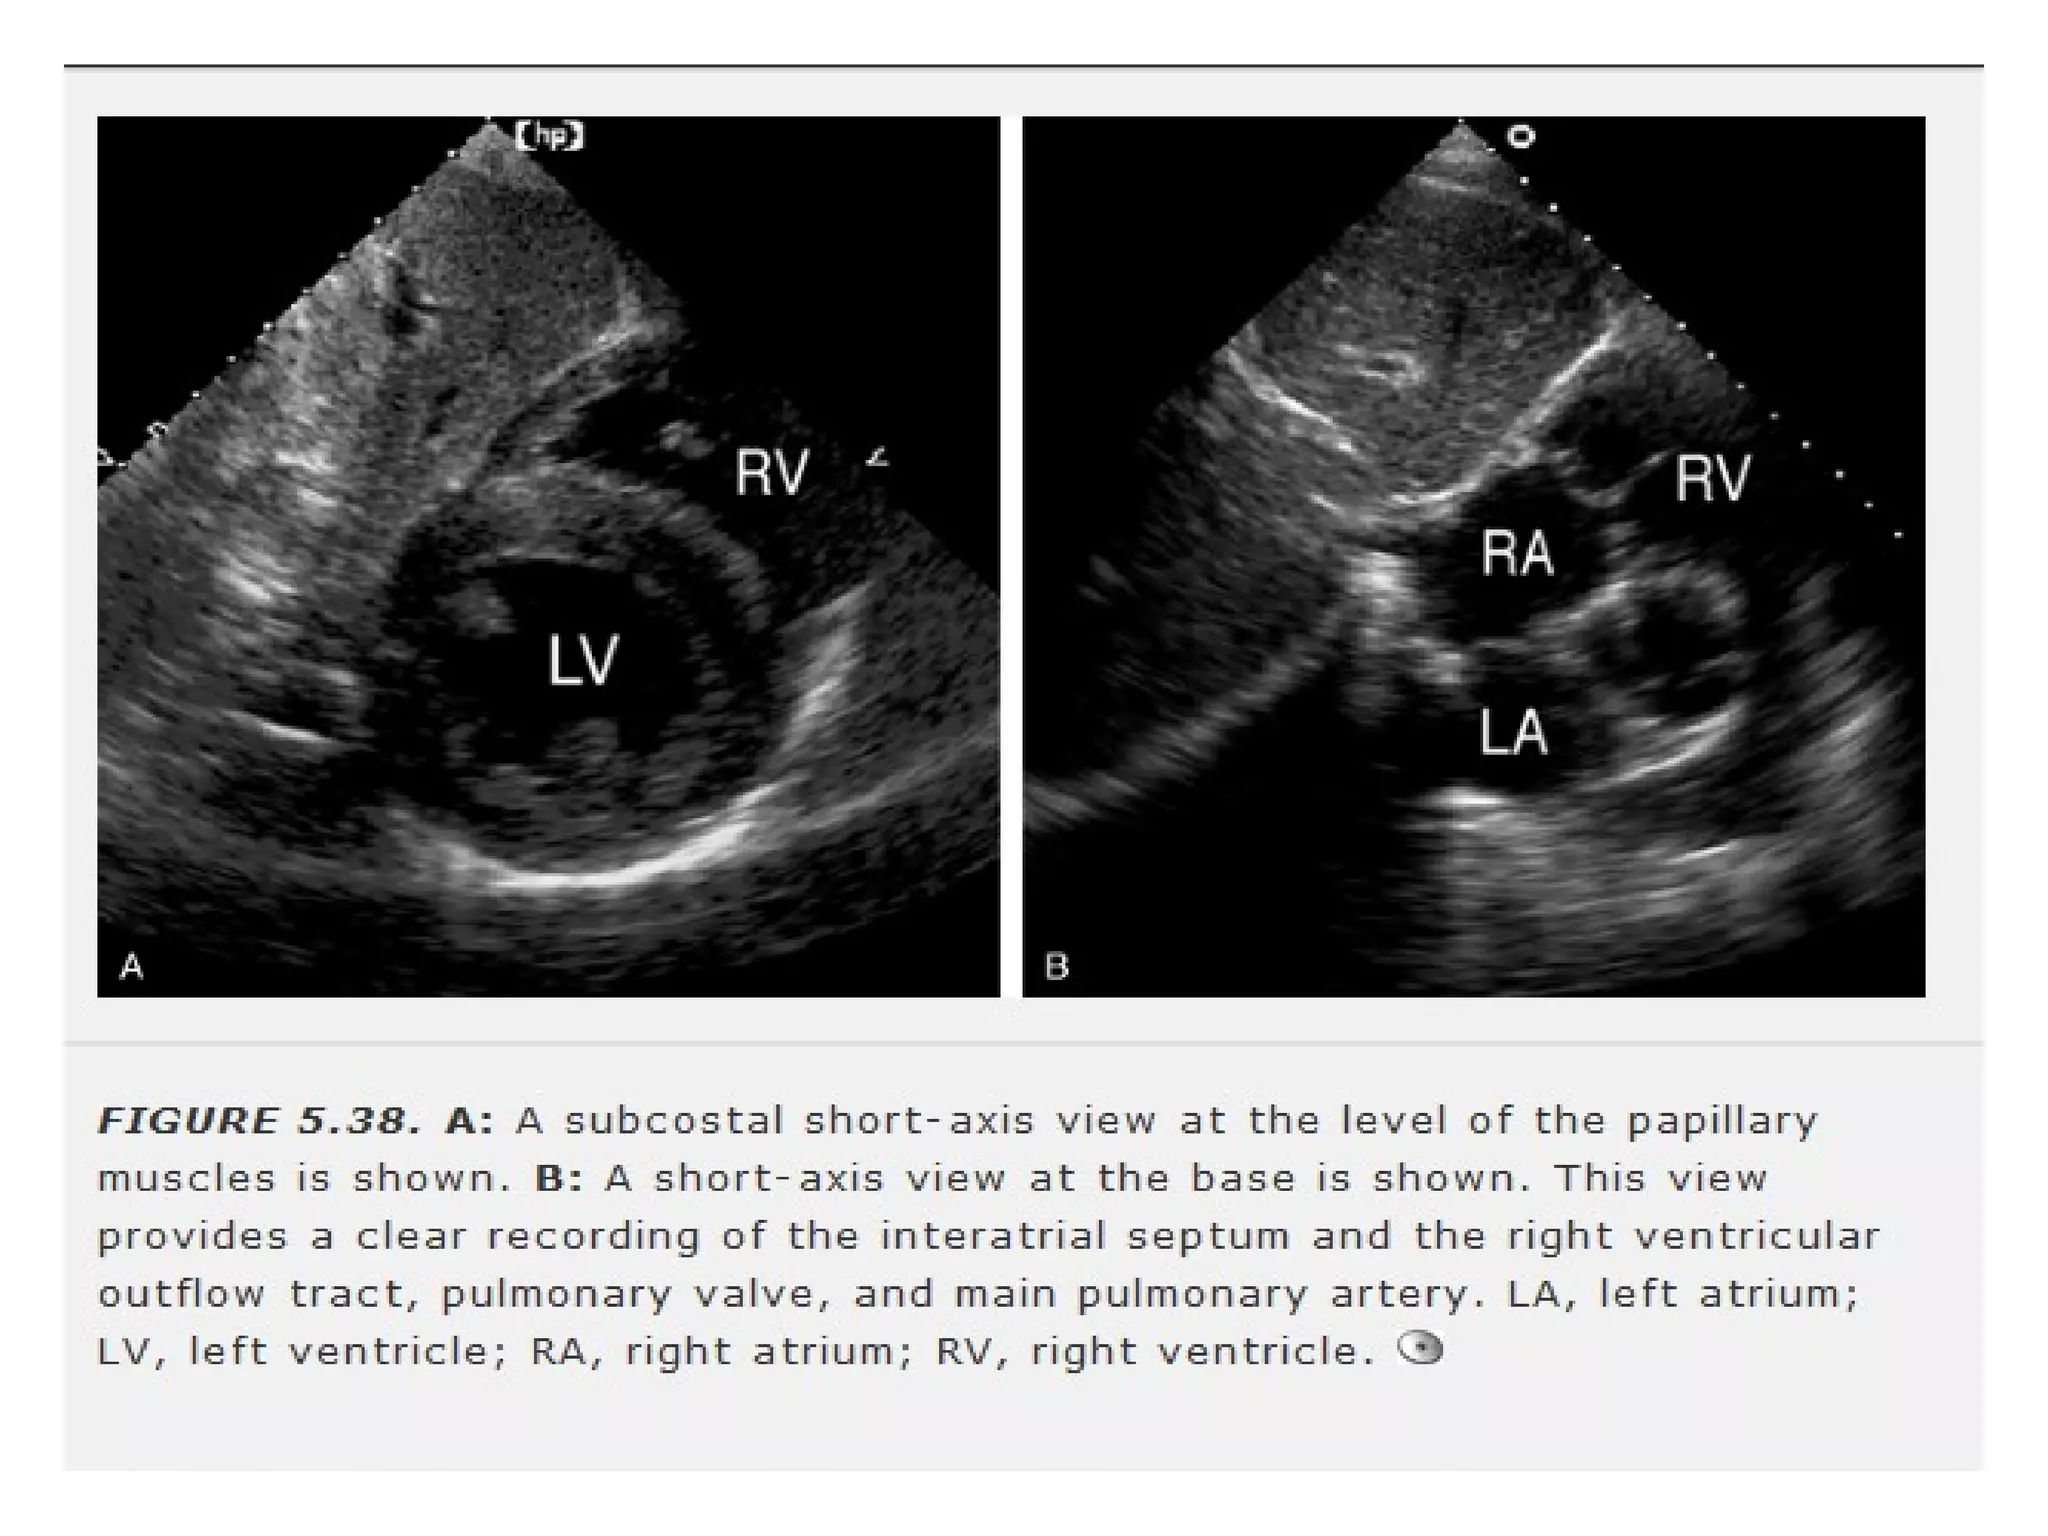

• beam is oriented perpendicular to long

axis of LV

• better endocardial definition

• septal defects are better delineated.

• Only view that visualises superior portion

of IAS

• proximity of RV free wallto the

transducer(pericardial tamponade)

• IVC & hepatic veins are viewed.